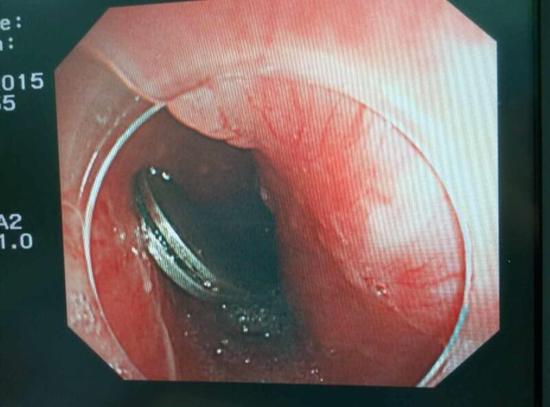

手術(shù)中,范醫(yī)生通過胃鏡準(zhǔn)確發(fā)現(xiàn)了胃里的鑷子。但讓他驚訝的是,在華先生胃底竟然還躺著三個(gè)被腐蝕了的打火機(jī),打火機(jī)的金屬部件都已經(jīng)不見了。

隨后,范醫(yī)生先用圈套器套取出了長(zhǎng)10厘米的鑷子,再一個(gè)一個(gè)地取出了打火機(jī)。整個(gè)取出過程小心謹(jǐn)慎而又一氣呵成,只用了不到10分鐘。

“真的是太危險(xiǎn)了?!狈夺t(yī)生表示,鑷子前端比較尖銳,一旦刺穿胃前壁,又有可能刺破肝臟,引發(fā)臟器受損和大出血。而打火機(jī)在胃內(nèi)酸性胃液腐蝕后,不 僅塑料外殼有毒,打火機(jī)內(nèi)的燃料一旦發(fā)生泄露會(huì)有灼傷胃腸道的危險(xiǎn)。打火機(jī)頭端還有尖銳金屬部件,若嵌頓或劃傷腸道會(huì)誘發(fā)腸梗阻、腸穿孔、消化道出血等嚴(yán) 重并發(fā)癥。